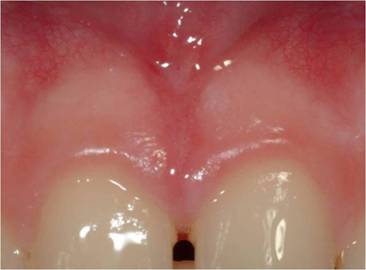

Oral surgery. This group comprised 5 patients. The Laser settings were: fluence between 5 and 15 J/cm2, variable pulse length between 20 and 60 ms, and a spot diameter less than 1mm in frenulectomy. Oral tissues were treated without local intra-tissue anaesthesia [17].

The patients described the procedure as totally painless [Fig.4a]. All patients returned to their routine activities without delay.

Figure 4

a: upper lip frenulum pretreatment. b: upper lip frenulum immediatedly post treatment. c: upper lip frenulum 10 days after treatment

Int J Med Sci Image Int J Med Sci Image Int J Med Sci Image

No haemorrhage was observed either during treatment or during the healing period.

In all oral surgical procedures, no haemorrhage was observed either during treatment or during the healing period. No sutures were required. The patients were comfortable with no pain, either intra-operatively or post-operatively. Haemostasis was optimum immediately after the procedure [Fig.4b]. Ten days later the procedure, each healing was found to be uneventful [Fig.4c].